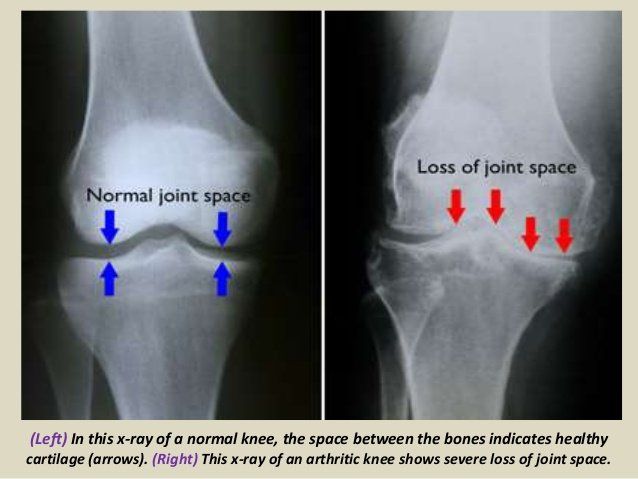

Osteoarthritis is one of the most common medical conditions in the world and is commonly referred to as “wear and tear” degenerative joint disease. It typically results from the gradual loss of cartilage within/between joints. This cartilage serves as a type of shock absorber preventing direct shear force and “bone on bone” pressure. Once the shock-absorber is gone it will slowly lead to inflammation and erosion of the joint.

So now let us focus on some of the clinical presentations of Osteoarthritis (OA). In general there is a marked variability of disease expression. Although most patients present with joint pain and functional limitations, the age of disease onset, sequence of joint involvement, and disease progression vary from person to person. OA ranges from an asymptomatic, incidental finding on clinical or radiologic examination to a progressive disabling disorder eventually culminating in "joint failure" with impaired mobility and quality of life.